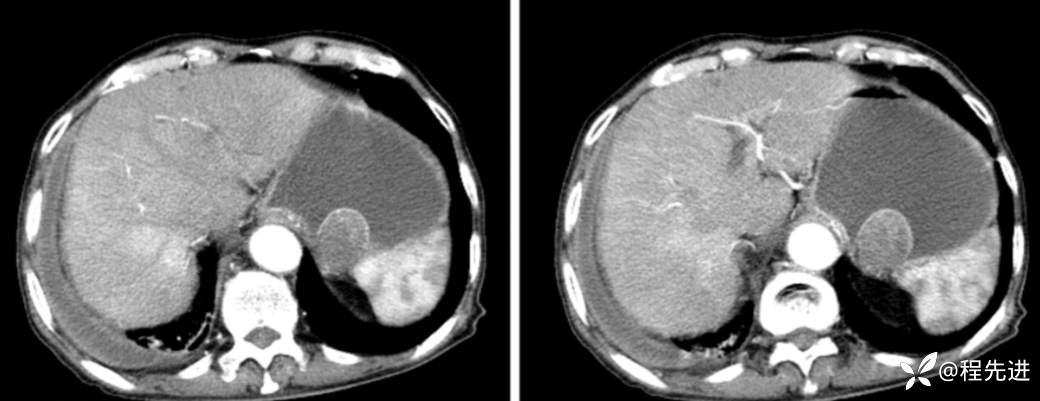

动脉期

门脉期